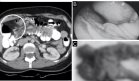

Se presenta el caso de una mujer de 21 años con antecedentes de hipertensión arterial y feocromocitoma metastásico con diseminación a vejiga, huesos y pulmones. La paciente tiene antecedentes familiares de neoplasias endocrinas, con diagnóstico de feocromocitoma en su padre y hermana, y cáncer de páncreas en su abuela. Fue admitida en el hospital debido a hipertensión no controlada y síntomas crónicos relacionados con su enfermedad.

La paciente había sido sometida a suprarrenalectomía derecha a los 10 años y recibía tratamiento con análogos de somatostatina y radioterapia paliativa. Su medicación incluía doxazosina, labetalol, oxibutinina, aceite de parafina y nifedipino.